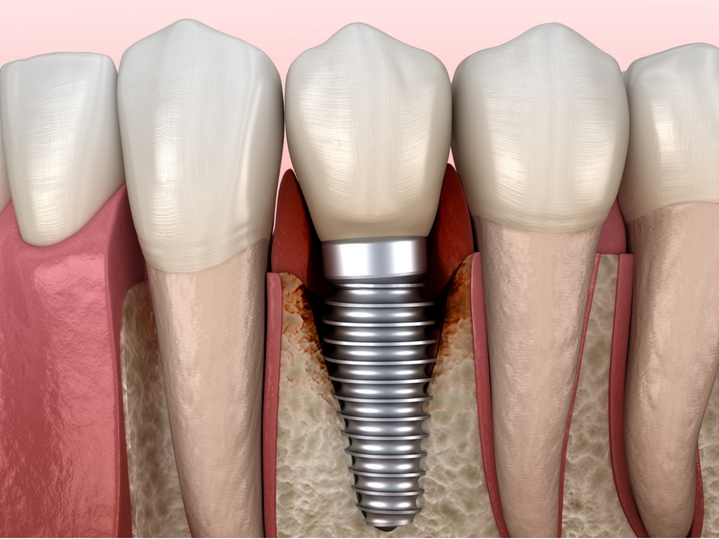

Vi khuẩn xâm nhập vào khoảng sâu giữa implant và nướu,

sẽ ăn chất thải thức ăn và sinh sôi nảy nở, gây viêm và phá hủy mô xương xung quanh.

Tình trạng này được gọi là 'viêm quanh implant'.

Viêm xung quanh Implant

Nếu viêm quanh implant không được điều trị, mô xương xung quanh implant sẽ phá hủy

và dần trở nên thấp hơn. Ngoài ra, trụ implant cuối cùng có thể bị rơi và thậm chí

cả những chiếc răng tự nhiên xung quanh cũng có thể bị rụng.

Bệnh viêm quanh implant này càng nguy hiểm hơn vì không có triệu chứng gì đáng chú ý.

Điều này là do trụ implant không được kết nối với các dây thần kinh nên không cảm thấy đau.

(Răng thật có dây thần kinh nên cảm thấy đau, nhưng implant không có dây thần kinh nên không có cảm giác đau.)